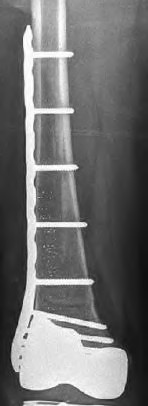

A 72-year-old female presents with acute thigh pain and an inability to bear weight after a minor fall, 10 years post-THA. Radiographs demonstrate a fracture around the tip of the well-fixed femoral stem, extending into the diaphysis. The bone stock proximally remains intact. Which principle must be strictly adhered to during the surgical fixation of this fracture?

A 68-year-old male sustains a distal femur periprosthetic fracture (Lewis and Rorabeck Type II) directly above a well-fixed PS TKA femoral component. The fracture is displaced. What is the most appropriate management?

A 75-year-old female sustains a periprosthetic femur fracture around a cemented polished taper slip stem. Radiographs demonstrate a fracture around the tip of the stem. The stem is radiographically loose, but the proximal bone stock is excellent (Vancouver B2).